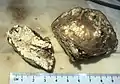

Gross pathology of a large tophus

Gross pathology of a large tophus Micrograph of a gouty tophus